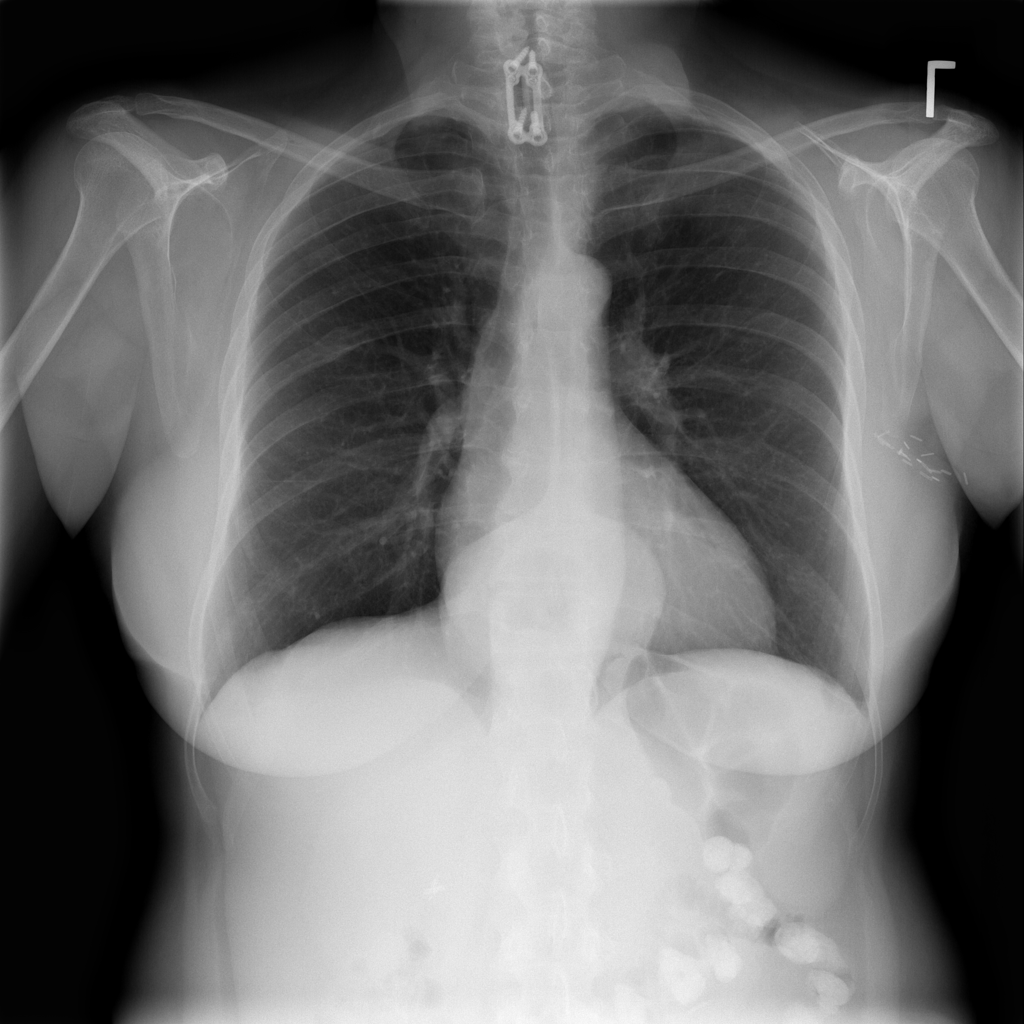

PAT-C048 · IMG-001Hernia

PAT-C048 · IMG-001

PA